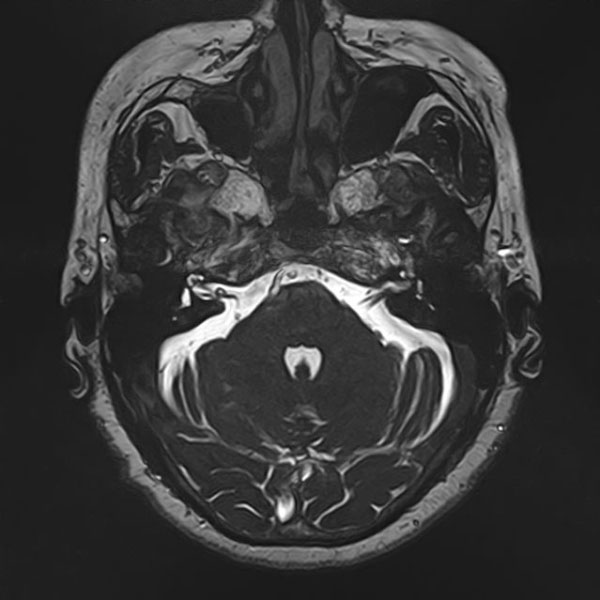

手術前

(MR1)